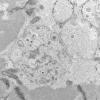

Pompe Disease (4)